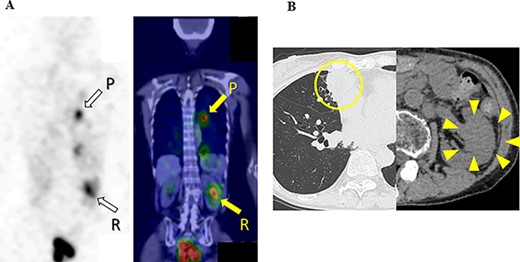

131I scintigraphy and CT images of the chest and abdomen after the second surgery; (A) in 131I scintigraphy, some lung metastases showed radioiodine uptake, whereas others did not. Radioiodine uptake was also observed in the left renal tumor, but not in the right kidney; left: RAI scintigraphy, right: SPECT–CT, P: pulmonary metastases, R: renal metastasis; (B) pulmonary and renal metastases both increased in size.

Ten months after the start of lenvatinib, CT showed a decrease in the sizes of pulmonary metastases (Fig. 3A) and renal metastasis (Fig. 3B) (tumor reduction rate: 45%). Remnant thyroid resection was performed and followed by RAI therapy with 100 mCi. In 131I scintigraphy, some lung metastases showed radioiodine uptake, whereas others did not. Radioiodine uptake was also observed in the left renal tumor, but not in the right kidney (Fig. 4A); therefore, the left renal tumor was finally confirmed as renal metastasis of PTC. Since the sizes of pulmonary and renal metastases both increased after the RAI therapy (tumor growth rate: 71%) (Fig. 4B), the administration of lenvatinib was resumed from a dose of 4 mg/day. After resuming lenvatinib, she has been in SD status for 6 months.